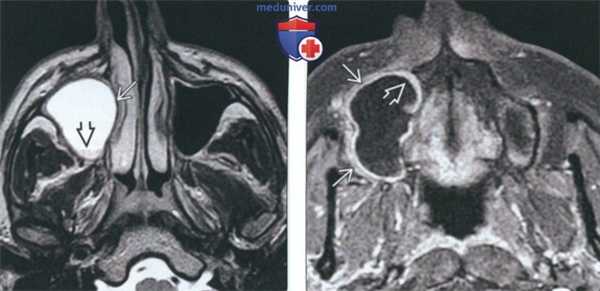

(Справа) При корональной КТ без КУ определяется легкое расширение нижней челюсти в области угла, обусловленное кератокистозной одонтогенной опухолью, и более выраженное расширение, а также истончение кортикального слоя выше (в области дуги). (Слева) При МРТ Т1ВИ в аксиальной проекции в нижней челюсти визуализируется неоднородное объемное образование, нарушающее целостность кортикального слоя и распространяющееся в жевательные мышцы. Участки с гиперинтенсивным сигналом в образовании, наличие которых является типичным признаком кератокистозной одонтогенной опухоли, обусловлены кератиновым дебрисом.

о Сигнал от промежуточной до высокой интенсивности, обусловленный орто- или паракератозом и (или) кровоизлиянием

о Неоднородный сигнал низкой или высокой интенсивности

о Тонкий «ободок», не накапливающий контраст; отсутствие солидного образования

о Контрастное усиление выражено больше, чем при рецидиве КОО